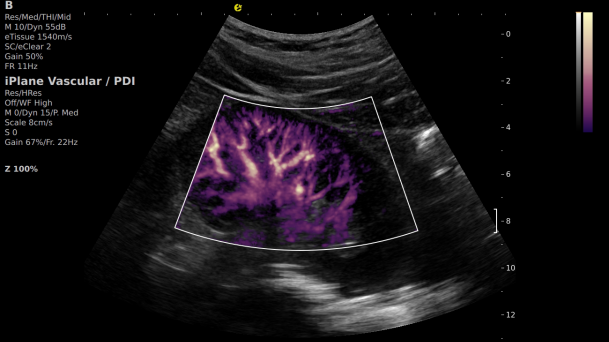

在肾移植领域,医生最怕的不是手术刀下的惊心动魄,而是那些手术后肉眼看不见的危机——急性排斥反应导致的血小板聚集形成的微血栓、毛细血管网损伤等...这些“隐形杀手”曾让无数移植肾在悄无声息中衰竭。而新航娱乐医疗(ESI)的iPlane Vascular平面波超微细血流显像技术,正是为破解这一难题而生。

这项革命性技术通过三大创新实现质的飞跃:

1) 基于OmniSound?平面波超快速平台,超声信号采集帧频提高了200倍(25000Hz)。

2) 可检测20-50μm级细小血管低速血流信号,能看清头发丝1/2粗细的微血管;

3) 通过血管指数(VI)定量评估局部血管密度,以定量化数据实时监测血流灌注情况,预判肾功能恢复情况;

超微视血流显像显示肾脏五级血管